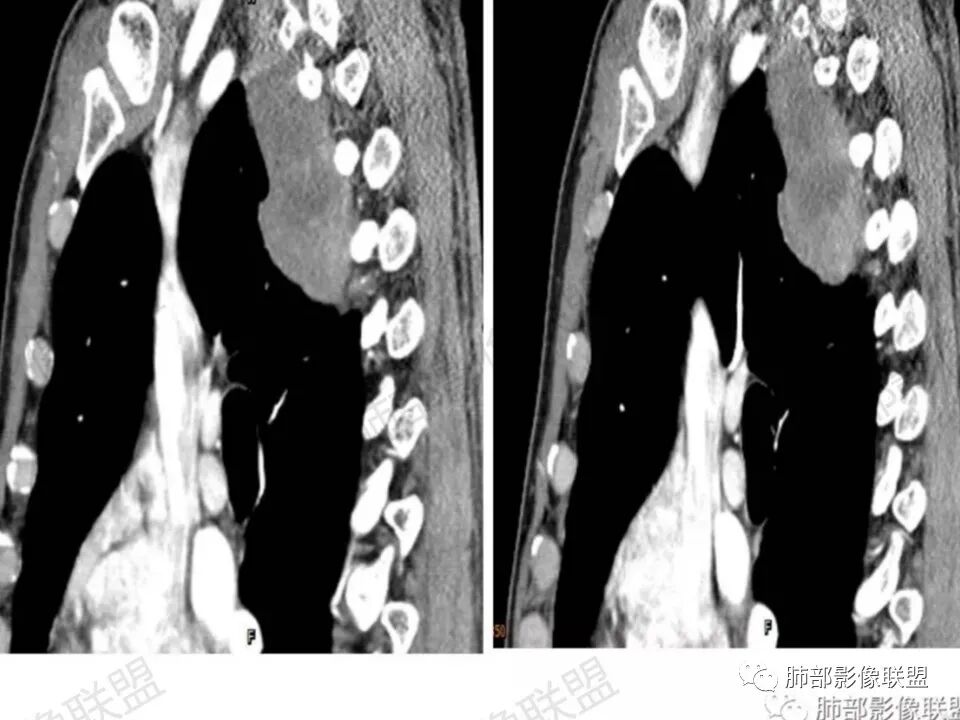

男,45岁,反复背痛3年;病程长,发展缓慢;后纵膈,与脊柱关系说不清;强化明显,有分区;诊断:神经源肿瘤;良性鉴别:间质来源肿瘤。

右侧后纵隔肿块,宽基地附着与胸膜,可见胸膜尾征,与肺组织交界清晰,没有平扫,增强后不均匀明显强化,部分可见向椎孔延伸,综合考虑:神经源性肿瘤(神经鞘瘤,神经节细胞瘤),鉴别孤立性纤维瘤

后纵膈肿块,边界清晰,增强后呈不均匀明显强化,渐进性强化,并向椎间孔延伸,首先考虑良性,神经源性肿瘤,神经鞘瘤可能

右后纵膈肿块,脊柱旁,邻近椎间孔扩大向内延伸,密度不均匀,强化明显,考虑神经源性肿瘤,鞘瘤可能性大。

中年男,慢性病程,右后上纵隔脊柱旁肿物,呈D字型凸向肺部,见胸膜尾,定位肺外;肿物不规则强化,近脊柱边缘部分清晰可见脂肪间隙,部分与脊柱相连包绕,未见骨破坏,上方似延伸至颈部。定性良性,孤立性纤维瘤可能性大,鉴别神经鞘瘤。

这个病例定位肺外没问题,病灶呈宽基底,见明显的胸膜掀起征,定位胸膜或右后纵隔来源,而且肿块提示肋间动脉穿行,脏层胸膜来源可能性不大(脏层胸膜由肺动脉及支气管动脉供血),那就是壁层胸膜跟纵隔来源,但是图像上有2个层面是胸膜外间隙有受压推移,所以壁层胸膜来源也不考虑;病灶是渐进性强化,常见的就是间叶来源含有梭形细胞的软组织肿瘤跟后纵隔常见的神经源性肿瘤鉴别,那如何在后纵隔的大山里拨开云雾找到我们想要的答案呢?那小编在这里先理出几个问题: